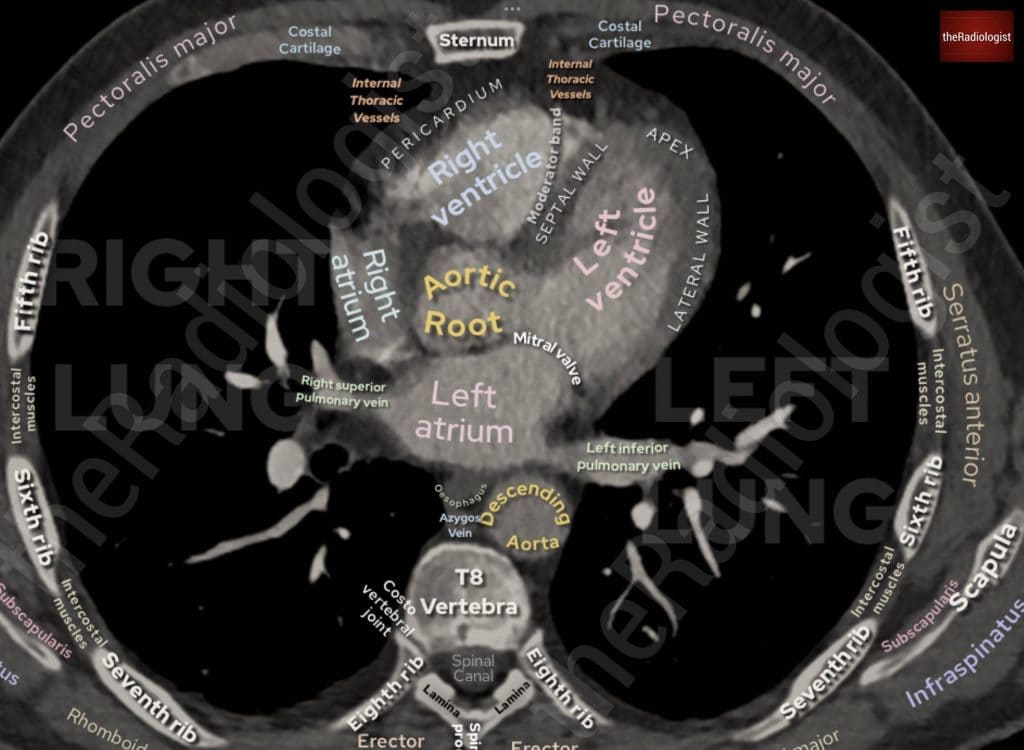

Anatomy review

Now let’s have a look at the scan and examine some anatomy. In every CT scan I review, I follow the contrast from where it was injected all the way into the heart and beyond. This ensures that I don’t miss anything along the way and also helps me identify pulmonary embolism (PE) on scans when we weren’t specifically looking for it (missing a PE is something you don’t want to do at any time as it can be a life threatening diagnosis).

Follow the contrast from the subclavian vein into the brachiocephalic vein on either the left or the right. This will then feed into the superior vena cava and into the right atrium. On a CTPA study, this should appear bright. The contrast will then pass through the tricuspid valve into the right ventricle.

Follow the brachiocephalic veins into SVC and then down into the right atrium. From here you can follow the contrast through the tricuspid valve into the right ventricle.

Follow the contrast up into the pulmonary trunk, which will split into two. I like to think this resembles an octopus with many flapping arms, although there are two main arms: the right pulmonary artery and the left pulmonary artery. It is then a matter of following these branches out into each lobe of the lung, and I prefer to zoom in when I do this. This just ensures each artery has not been missed.

Now, follow the contrast all the way out into the pulmonary arteries and then back into the pulmonary veins, which lead into the left atrium, through the mitral valve into the left ventricle, and then up into the aorta.

Annotated view of a CT chest showing the pulmonary veins draining into the left atrium.